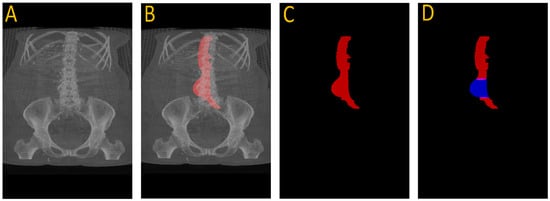

Figure 3 illustrates this full pipeline. Panel A shows the original CTA scan, while B displays the complete aorta mask generated by SAM2 after propagation over the input image. C shows the segmented mask from SAM2 output and finally, panel D highlights the aneurysm region using the manual annotation, with red indicating normal aorta segment and blue denoting the aneurysm segment. This visualization demonstrates how UNet and SAM2 operate in tandem: UNet anchors the aorta in normal regions, and SAM2 tracks it seamlessly across the aneurysm segments for full-volume segmentation. Figure 4 provides a cross-sectional view at the aneurysm’s start and end boundary, further illustrating the model’s performance.

Figure 4. Cross-sectional view of SAM2’s segmentation performance at the start (A) and end (B) boundaries of an aneurysm, where red shows the segmented region using UNet + SAM2 (refer to Figure 1 for anatomical reference).